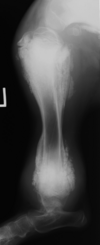

What is seen in these radiographs?

solid periosteal reaction